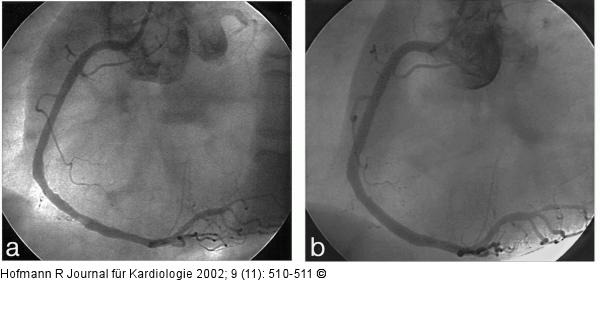

Abbildung 4b: Mobiler Thrombus der RCA bei NSTEMI Gleicher Koronargefäßabschnitt nach Stentimplantation: Füllungsdefekt nicht mehr nachweisbar. |

Abbildung 4b: Mobiler Thrombus der RCA bei NSTEMI

Gleicher Koronargefäßabschnitt nach Stentimplantation: Füllungsdefekt nicht mehr nachweisbar. |